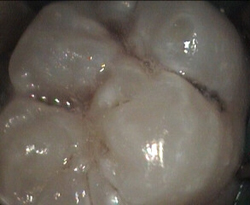

Unusual prevalent but superficial groove pattern on permenant molar after Sealed

unusual wide but superficial decay after